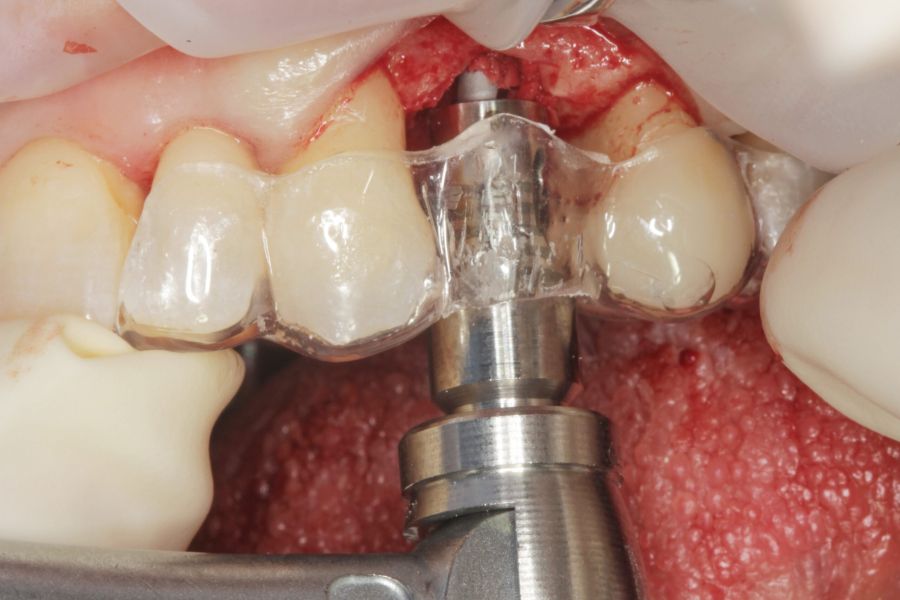

Todas las cirugías fueron realizadas por un único cirujano bajo anestesia local, tras un diagnóstico previo del lecho óseo mediante tomografía volumétrica (CBCT) procesada con un software específico de planificación implantológica (BTI-Scan III). La preparación del lecho implantario se llevó a cabo siguiendo la técnica de fresado biológico a bajas revoluciones descrita por Anitua y cols.19.

En cuanto a la rehabilitación protésica, en todos los casos se utilizó una prótesis atornillada con transepitelial para prótesis unitaria. La supervivencia de las prótesis fue del 100%, sin encontrarse fracaso en ninguna de ellas al igual que los implantes, con un tiempo de seguimiento de tres años. Durante el primer año, en las visitas de control, ninguno de los implantes mostró sangrado al sondaje ni inflamación de los tejidos periimplantarios. La media de la pérdida ósea en este punto fue de 0,32 mm (+/- 0,60) y la media de la pérdida ósea distal de 0,31 (+/- 0,48). A los dos años, no se registraron tampoco signos inflamatorios en ninguno de los implantes y la pérdida ósea mesial del conjunto fue de media de 0,38 mm (+- 0,54) y la distal de 0,64 mm (+/- 0,70). En la última visita a los 3 años, los tejidos periimplantarios siguieron estables, sin signos de inflamación y la media de la pérdida ósea mesial fue de 0,40 mm (+/- 0,53) y la distal de 0,69 (+/- 0,55) (Figura 5). En las Figuras 6-12 se muestra uno de los casos incluidos en el estudio.